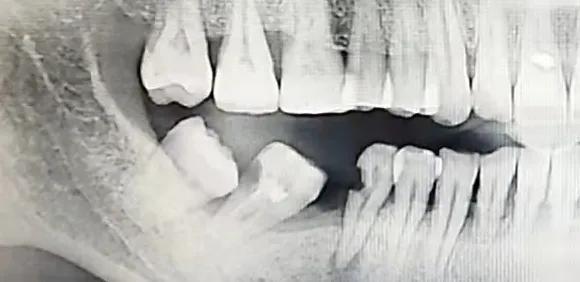

这个是我妈左侧最严重的部分:

左侧蛀牙拔出一颗后,由于常年的牙齿空缺进食导致本来的好牙发生了侧倾,还顶坏了另外一颗好牙。